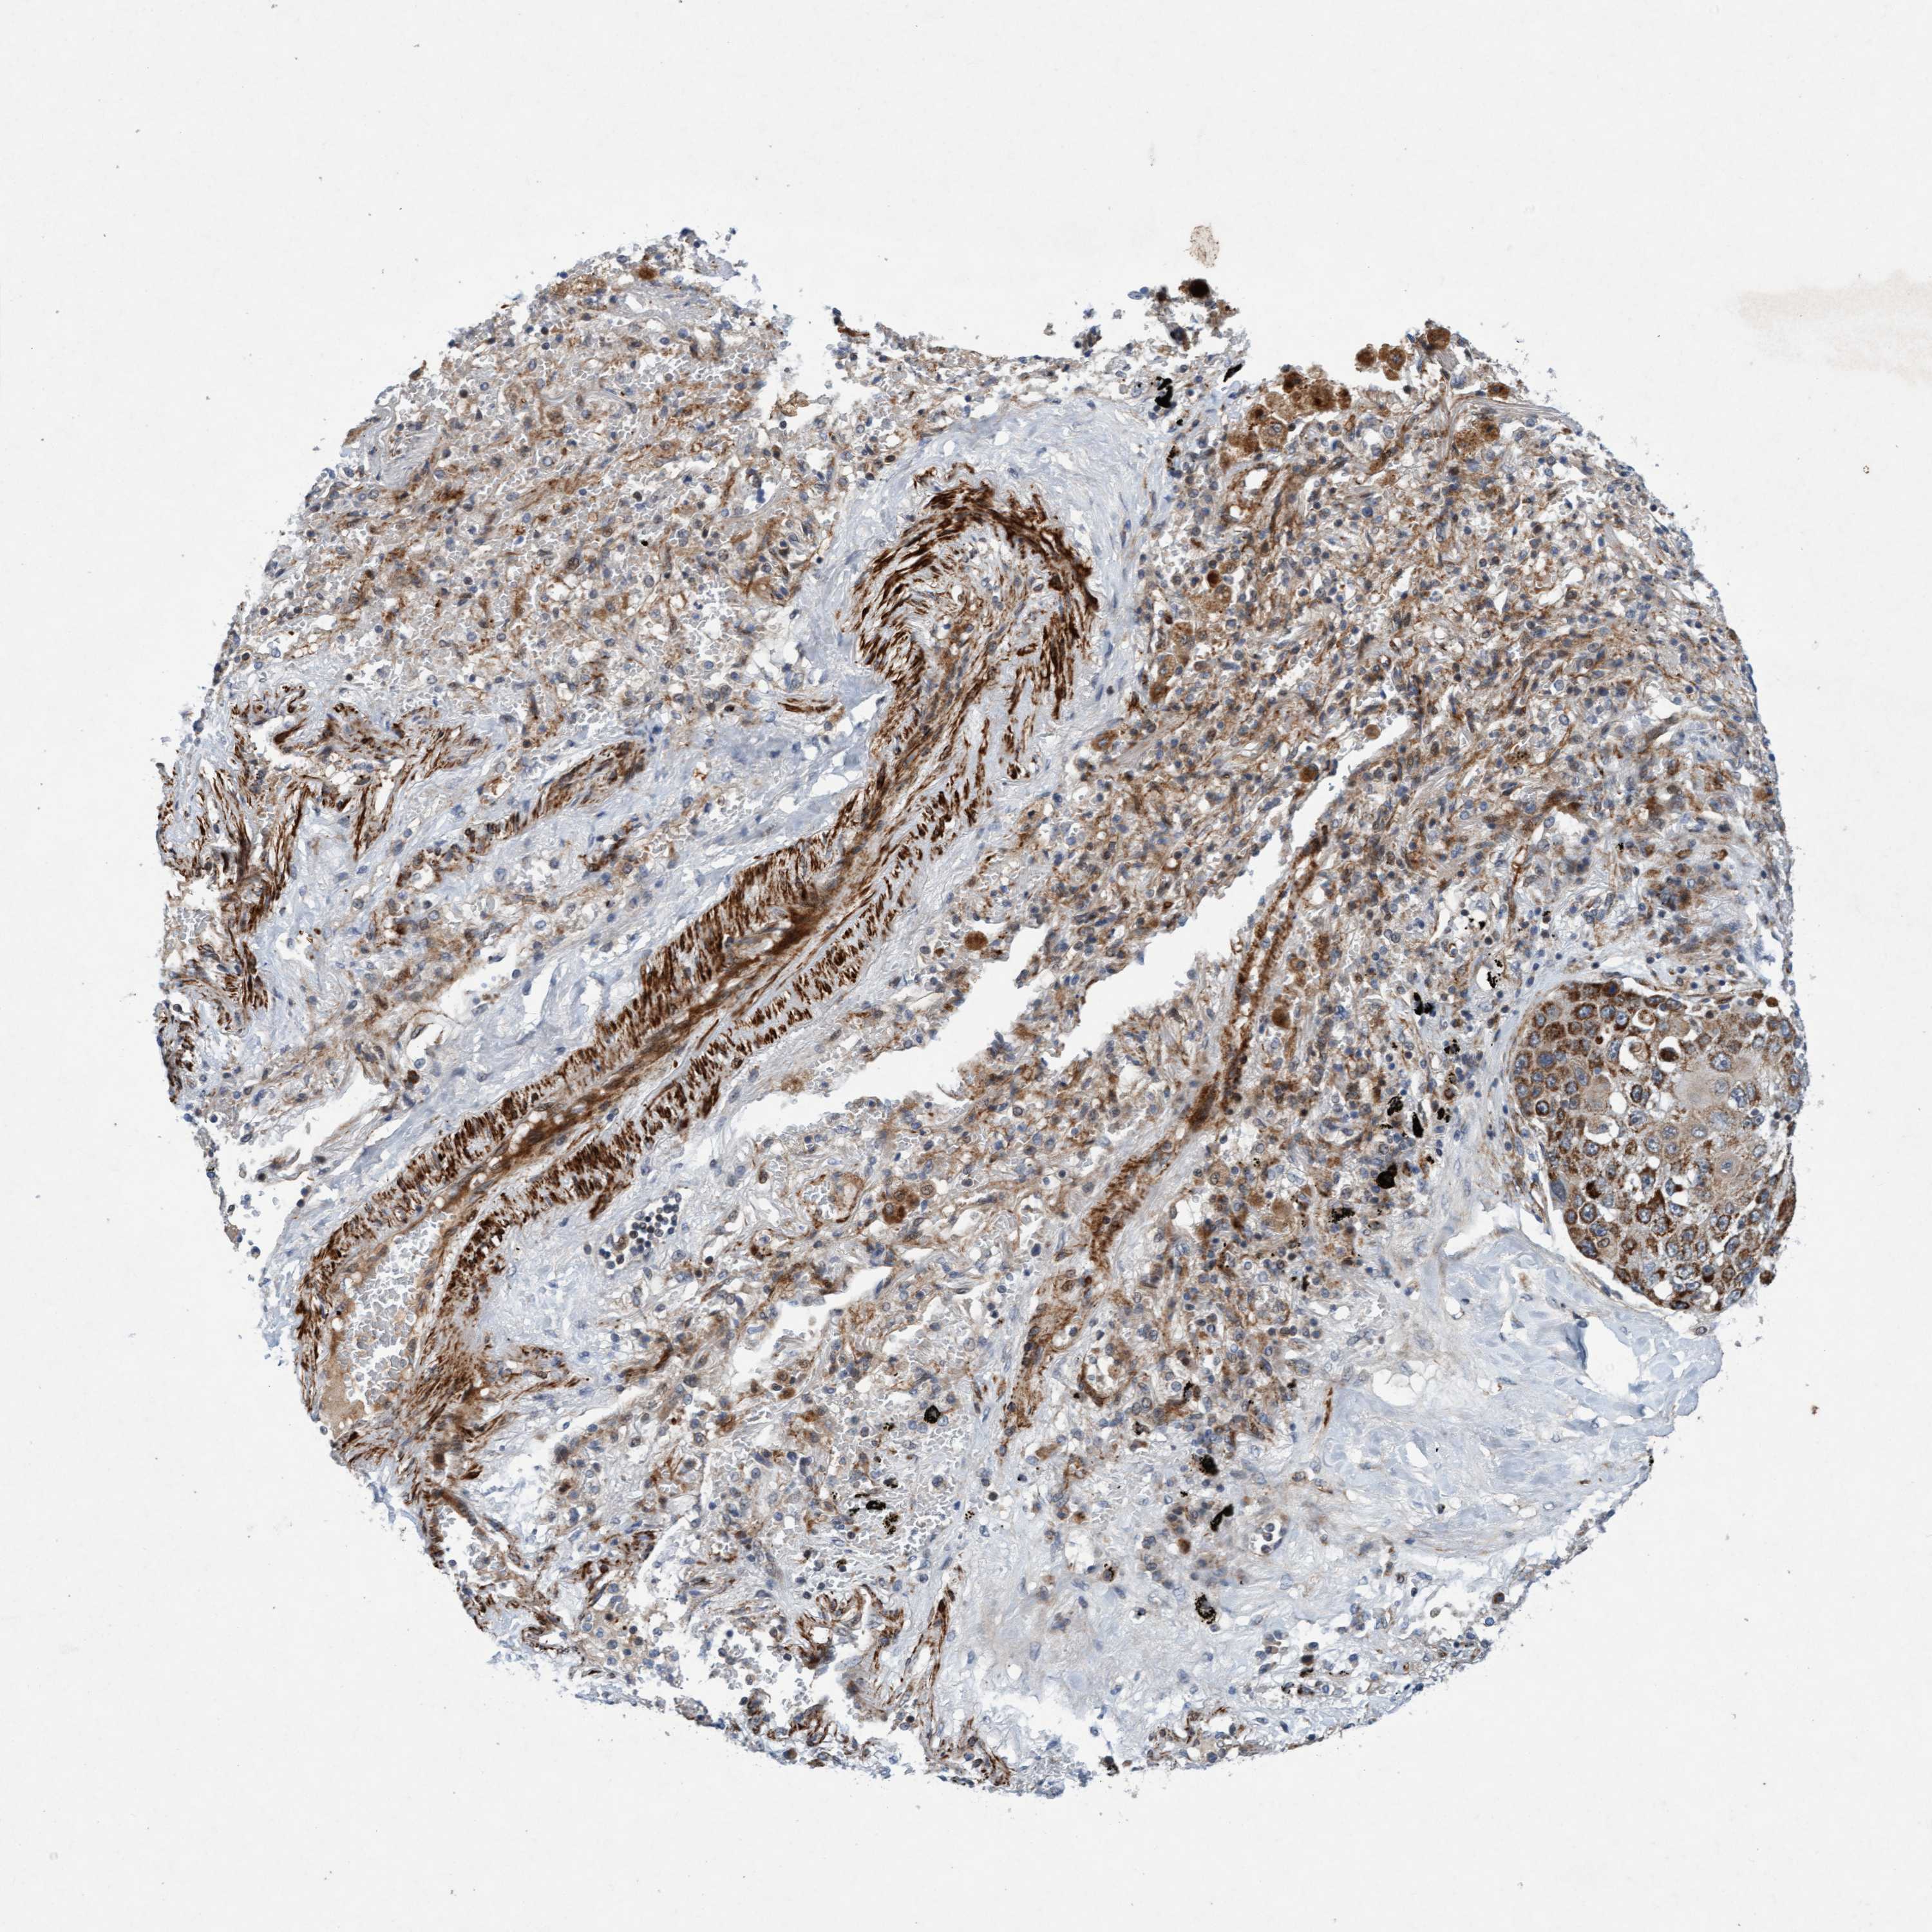

CANCER LUNG CANCER Show tissue menu